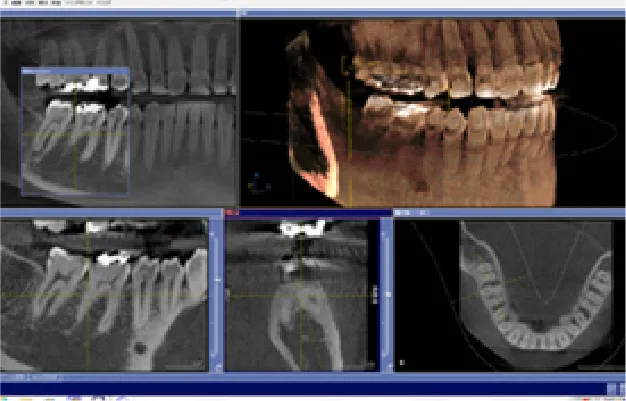

• 1検査・診断

レントゲンや問診の結果から、それぞれの患者様に適した装置をご提案させていただきます。 費用に応じた適切なプランをご用意いたしますので、お気軽にご相談ください。

検査・診断